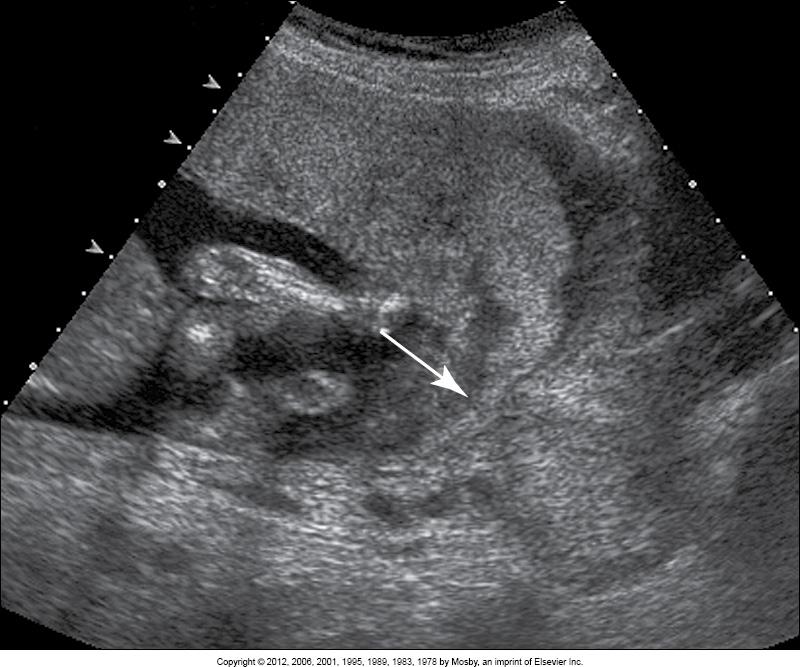

What does this image show?

marginal abruption